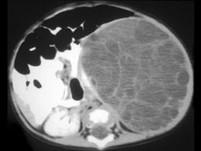

问题 男,5岁,左季肋部可触及一包块,请根据其影像,选择最可能的诊断 ( )

选项 A、左肾细胞癌 B、左肾多房性囊肿 C、左肾单纯性囊肿 D、左肾脓肿 E、左肾血管平滑肌脂肪瘤

答案 B